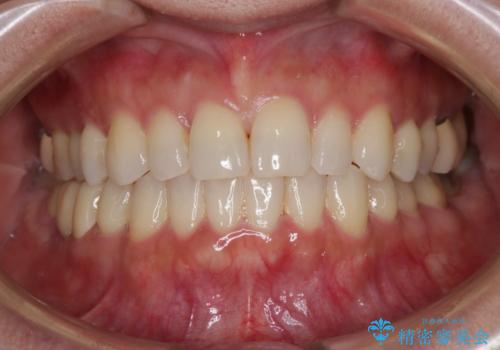

[ マウスピース矯正 ] がたがたした歯並びを治したい

担当医 大元洋佑